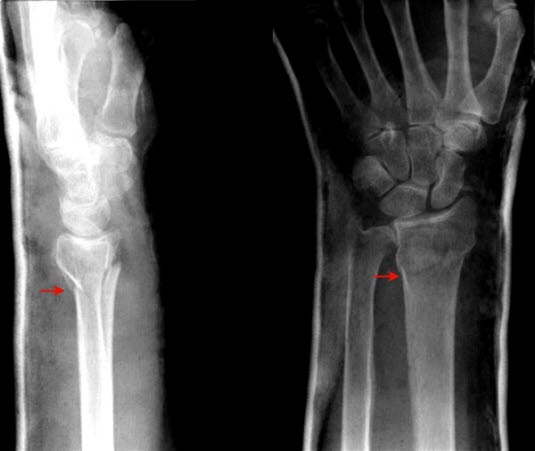

Beinbrudd

Det kreves en betydelig kraft for å brekke et bein, hvis da ikke beinet er svekket på forhånd av sykdom. Kraften kan være direkte, indirekte eller vridende. En direkte kraft, som et spark, vil brekke beinet på det stedet kraften treffer. Det vanligste beinbruddet er håndleddsbrudd etter fall. En indirekte kraft vil forårsake beinbrudd et stykke unna treffstedet. For eksempel vil et fall på en utstrakt hånd kunne føre til brudd på kragebeinet. En vridende kraft kan også brekke et bein, for eksempel hvis foten setter seg fast og den påfølgende vridningen fører til ankelbrudd.

Bruddet kan være stabilt, der bruddendene står riktig mot hverandre, eller ustabilt, der bruddendene ikke står mot hverandre og kan beveges i forhold til hverandre. Ustabile brudd kan føre til at beinpipene stikker ut gjennom huden. Hvis en bruddende stikker gjennom huden, sier vi at bruddet er åpent. Hvis huden er inntakt, er bruddet lukket. Et åpent brudd innebærer en betydelig infeksjonsrisiko.